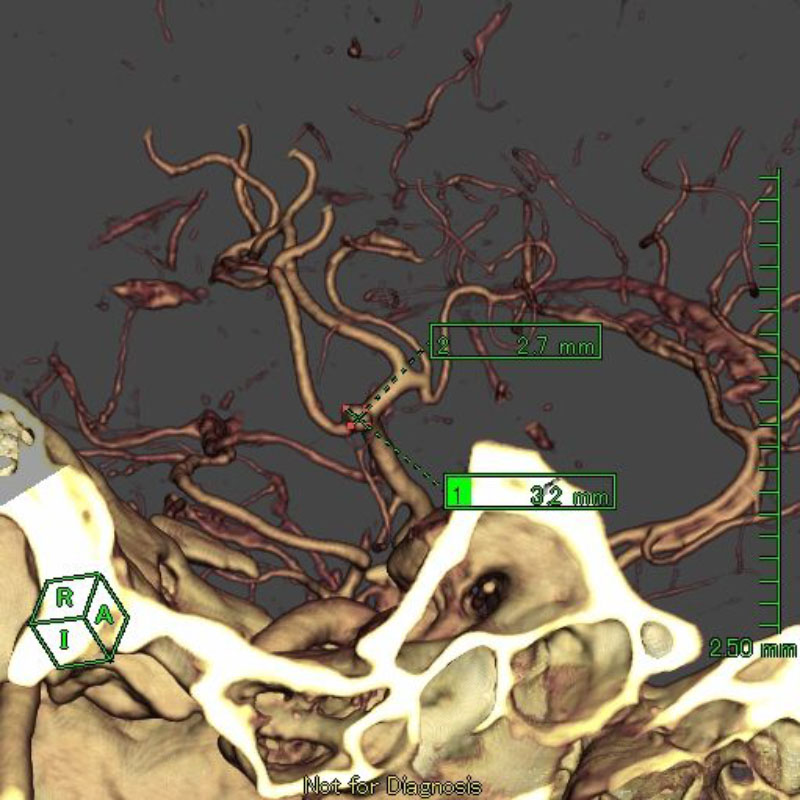

1

'26年1月

40代

右中大脳動脈瘤

クリッピング術

手術前

クリップ前

クリップ後

術後血管撮影